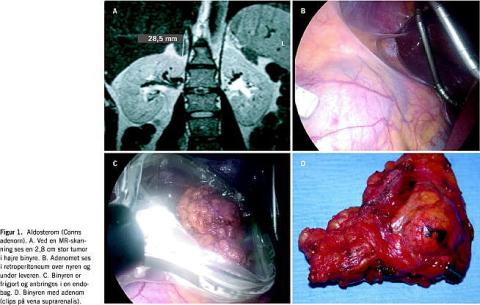

Aldosteromer er på grund af størrelsen på op til 2-3 cm særdeles velegnede til LA (Figur 1 ). Indlæggelsesvarigheden er typisk 1-3 dage, og mere end 90% kureres for hypertension [5]. Lignende resultater ses efter operation for incidentalomer, der som regel er 4-5 cm store. Operation for benigne adenomer hos patienter med mb. Cushing er generelt vanskeligere, dels er tumorerne ofte større (4-8) cm, og dels er patienterne ofte adipøse med vulnerable kar. Indlæggelsen er længere (3-6 dage) med langvarig followup pga. den supprimerede funktion af den raske binyre. Ved fæokromocytom forbehandles med alfablokker, indtil patienten er normotensiv. Tumorerne er meget karrige, men da de sjældent er over 5-6 cm i størrelse, kan de som regel fjernes laparoskopisk. Stort set alle bliver kureret for de typiske hypertensive anfald [5].